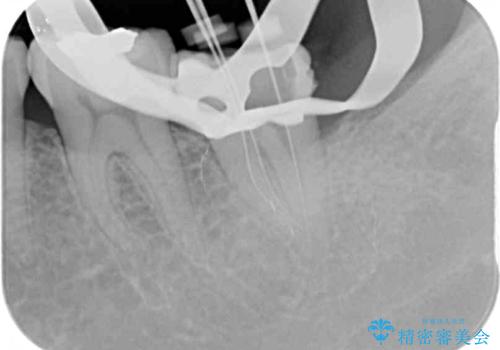

診察の結果、神経を取り除く必要があると判断されたため根管治療を行いました。

その後、左上の奥歯にも咬合時の痛みが認められ、レントゲン写真より歯内の神経が失活していることが分かりました。

2歯ともに根管治療を行い、その後はオールセラミッククラウンにて補綴治療を行うこととしました。